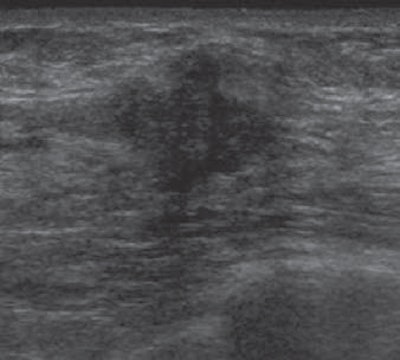

| Targeted ultrasound image above reveals solid mass with irregular shape and indistinct and angular margins. BI-RADS 5 assessment was made. Histopathology from ultrasound-guided core needle biopsy showed invasive ductal carcinoma. |